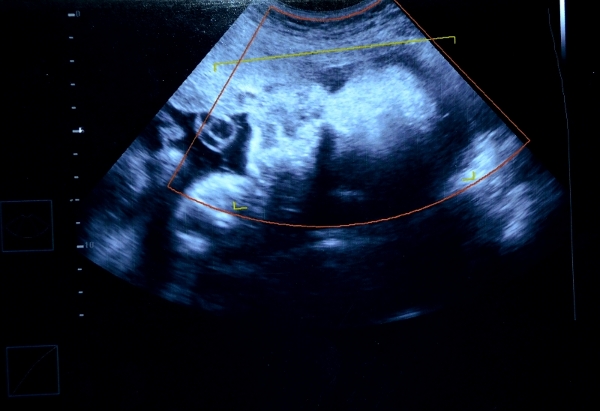

обычная 2Д